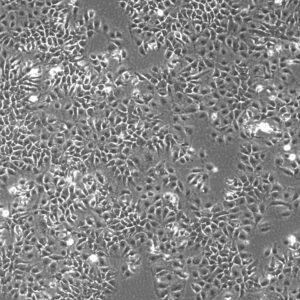

Morphology: Epithelial-like

Growth Properties: Adherent

Description: HuH7 was established in 1982 by Nakabayashi et al. from a 57-year-old Japanese male with well differentiated hepatocellular carcinoma.